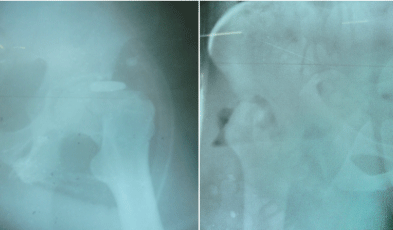

All patients showed complex proximal femoral fractures. Patient two and three also showed an open fracture type Gustillo 3a. Preoperative radiographs showed no signs of bone consolidation in all three patients within a time lapse of eight weeks between trauma and GRA (Figure 1).

Figure 1. Patient 1, pre- and postoperative x-ray

Pre-GRA all patients showed closed skin conditions on the injured hip. Furthermore, patient two and three showed no signs of systemic or local infection while patient one had intermittent fever but showed no signs of disseminated infection.